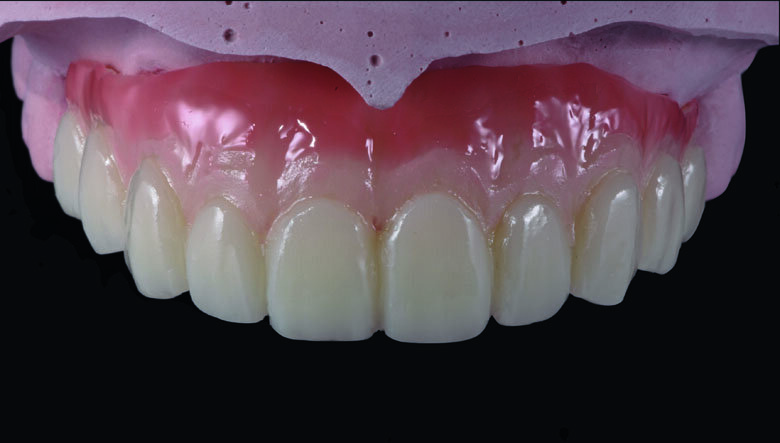

Fig 19. Completed Provisional Profile Prosthesis with gingival aesthetics that mimic nature

Provisional full arch bridge fabrication (Fig. 8 - 19)

Preparation cast with a diagnostic wax-up ca st was sent to a local laboratory for scanning and transforming into STL (Stereolithography) digital impression file. (Fig 8,9.) Two sets of STL impressions were super-imposed in the software in order to subtract the overlapping data. This process was done in order to transform the diagnostic wax-up into the STL digital impression. Consequently, the STL data was sent to the laboratory for milling. (Fig10.) A monochromatic milled-PMMA temporary bridge was fabricated in a local laboratory and returned to the dentist for composite layering. (Fig 11.) Gingival cutback was made to create sufficient gingival space for pink composite layering (Fig 12). Prior to composite layering CeraResin Bond 1 was applied and left for 10 seconds to prime the surface, followed by application of CeraResin Bond 2 for 10 seconds and light cured for 20 seconds (Fig 13.). Ceramage Indirect Composite gingival shade GUM-O (GUM Opaque) was applied to mask the color of PMMA (Fig 14.). GUM-D (GUM Dark) was applied on the attached gingiva area to the buccal flange (Fig 15.). GUM-L (GUM Light) was applied in the region of free gingiva (Fig 16.). F-GUM-R (Flowable GUM Red) and F-W (Flowable GUM White) were painted to mimic the mucogingival junction and vascular alveolar mucosa (Fig 17.) GUM-T (GUM Translucent) was applied to reproduce of reddish translucent gingiva areas (Fig 18) to achieve natural gingival aesthetics.

Contouring, Finishing and Polishing of temporary restoration

Meticulous finishing and polishing of the restoration is a crucial step to achieving the desired aesthetics. Dura-Green stone was used to contour the macro anatomical details while the Robot Carbide Fissure Bur was used to shape the interproximal and papilla areas. The course silicone points followed by Dura-Polishing paste Al2O3 with a medium strong brush was used to finish and pre-polish the restoration. Dura-Polish DIA, diamond polishing paste was applied with a fine brush followed by the cotton buff to achieve the final high-luster polishing (Fig 19.)1.